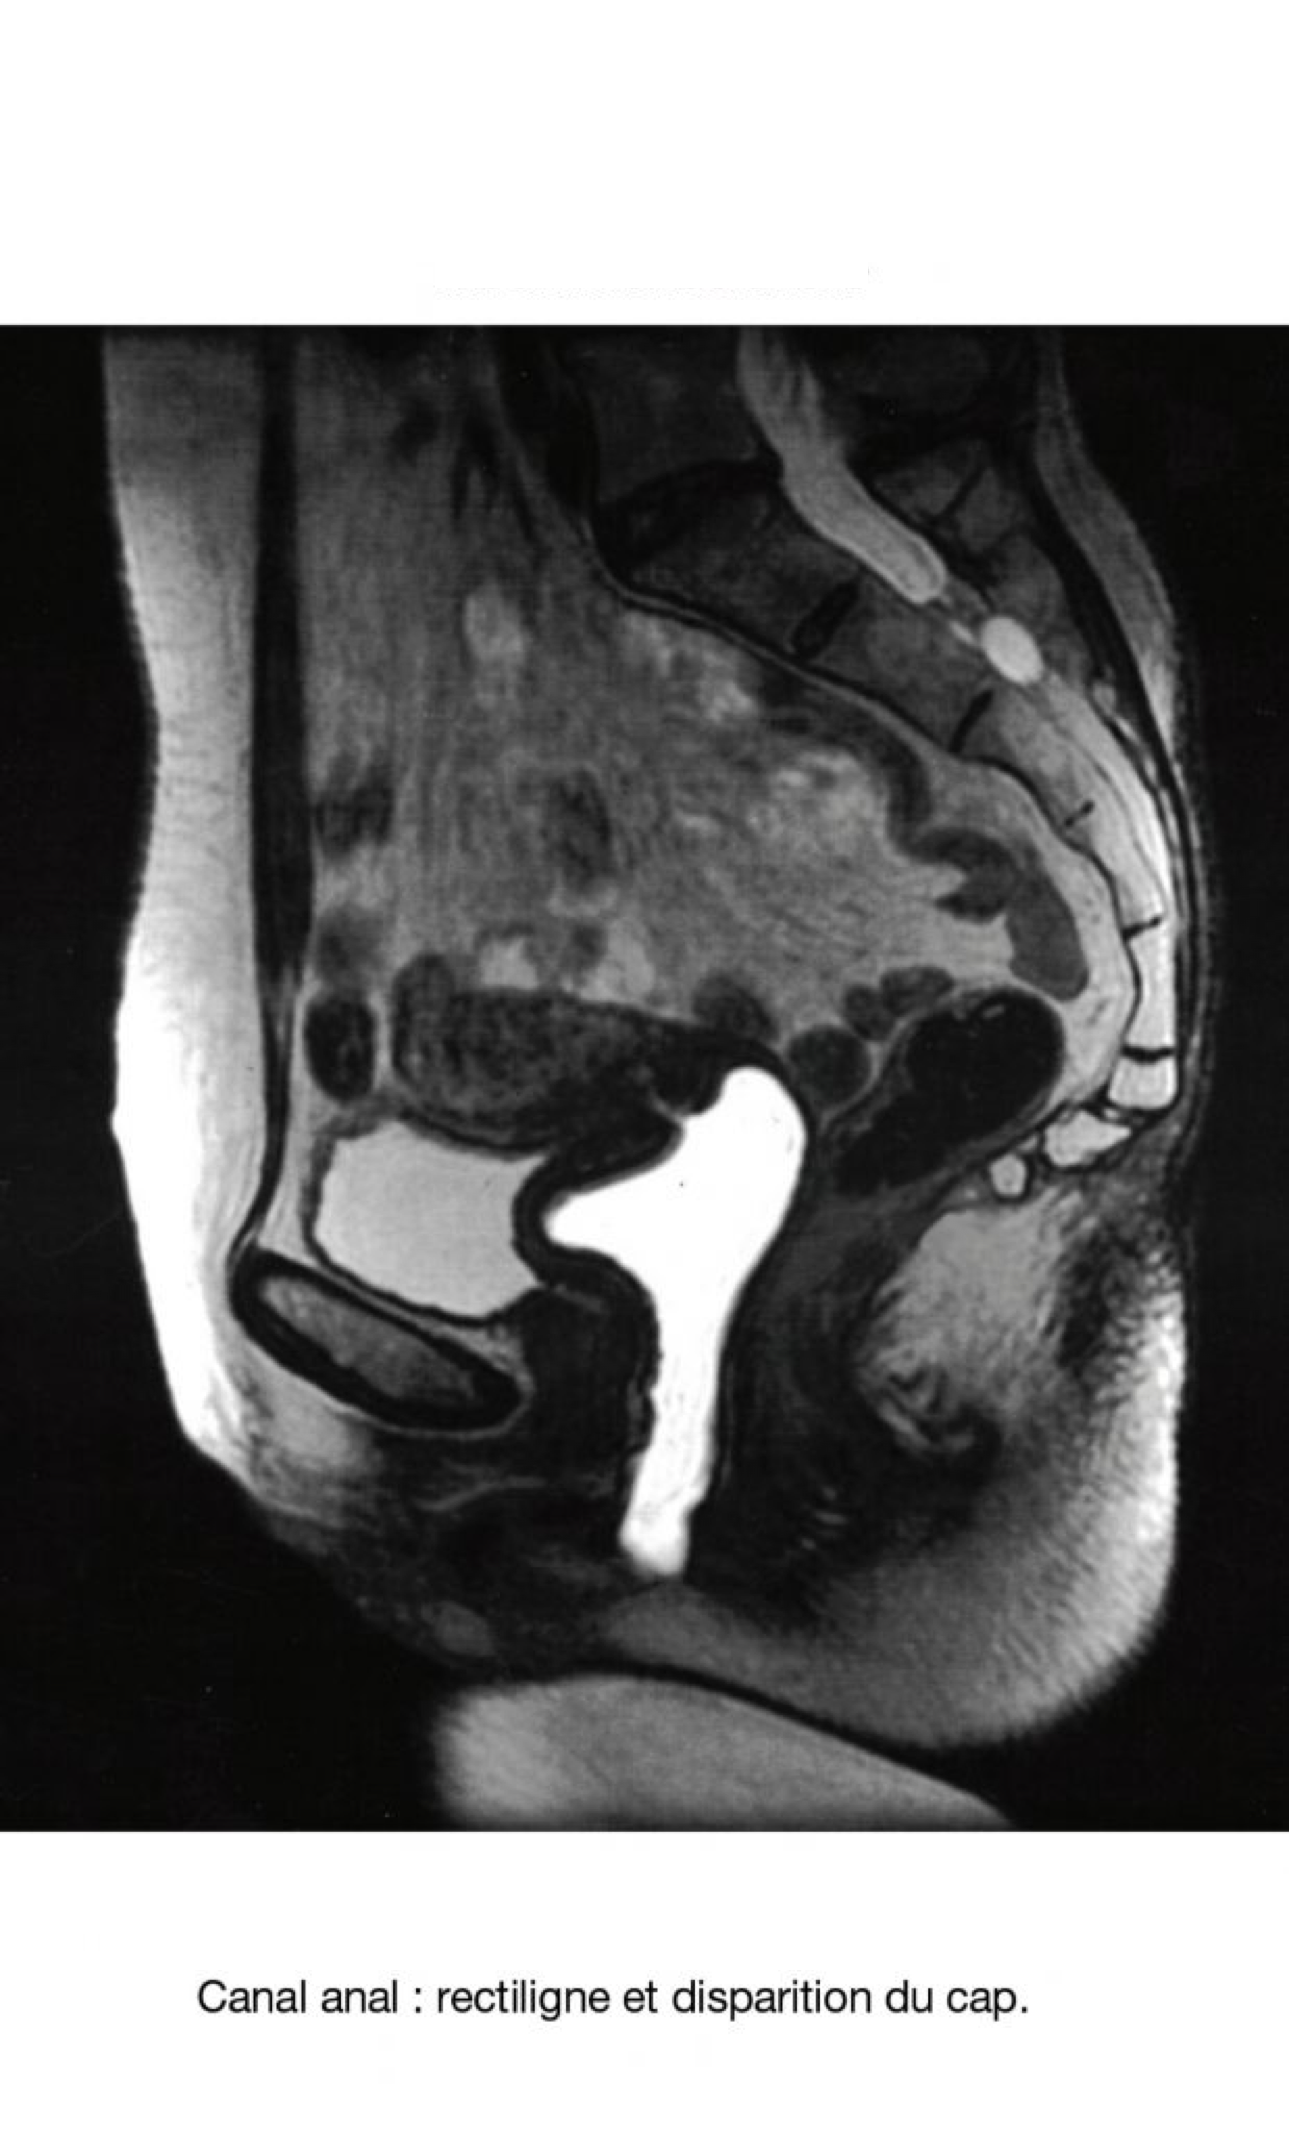

Pour le Canal Anal : la contraction périnéale accentue la plicature de l’angle ano rectal. Le relâchement l’efface. Les constipations fonctionnelles peuvent survenir par dyssinergie qui accentue la contraction du releveur au lieu de le relâcher pour exonérer. De fait le cap anal est tiré en haut et vers l‘avant. L’angle se ferme au lieu de s’ouvrir en rectiligne. A l’inverse, les images IRM de l’incontinence anale montrent un alignement ano-rectal.

17. Incontinence anale

Canal anal : rectiligne et (quasi) disparition du cap.

EN CAS D’INCONTINENCE, LE CANAL ANAL NE DÉCRIT PLUS UN ZIGZAG OCCLUSIF.